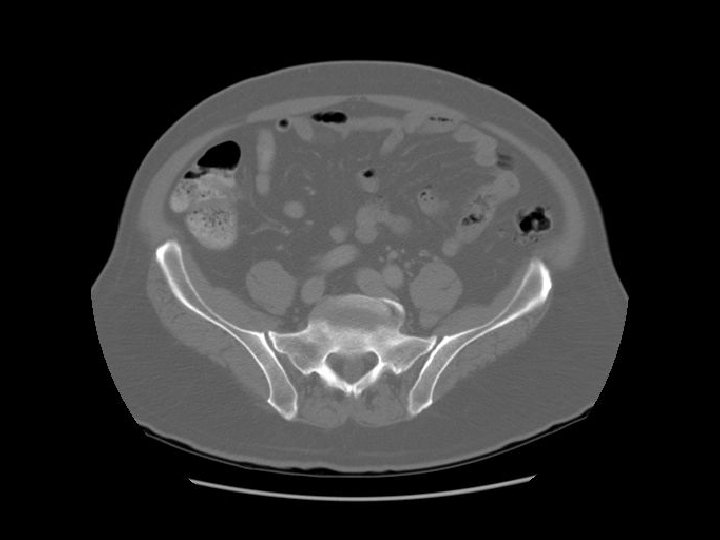

Abdominal aorta about to bifurcate.

Rt common iliac artery IVC Lt common iliac artery

L 5

Arrows are pointing to the common iliac veins joining to form the IVC. Left